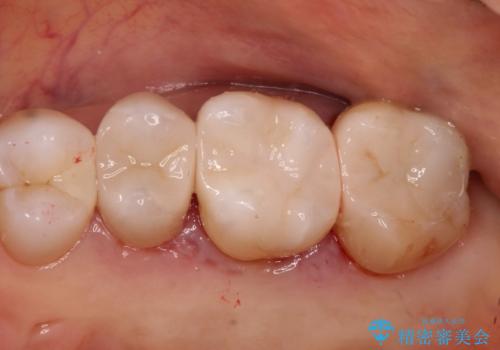

前歯の被せ物をやり替えたい

- 以前に被せ物の治療した箇所に汚れが溜まりやすいことを主訴に来院されました。

矯正治療を行なったのち、オールセラミッククラウンにて修復しております。